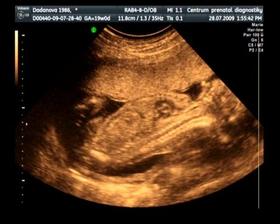

Naše maličké